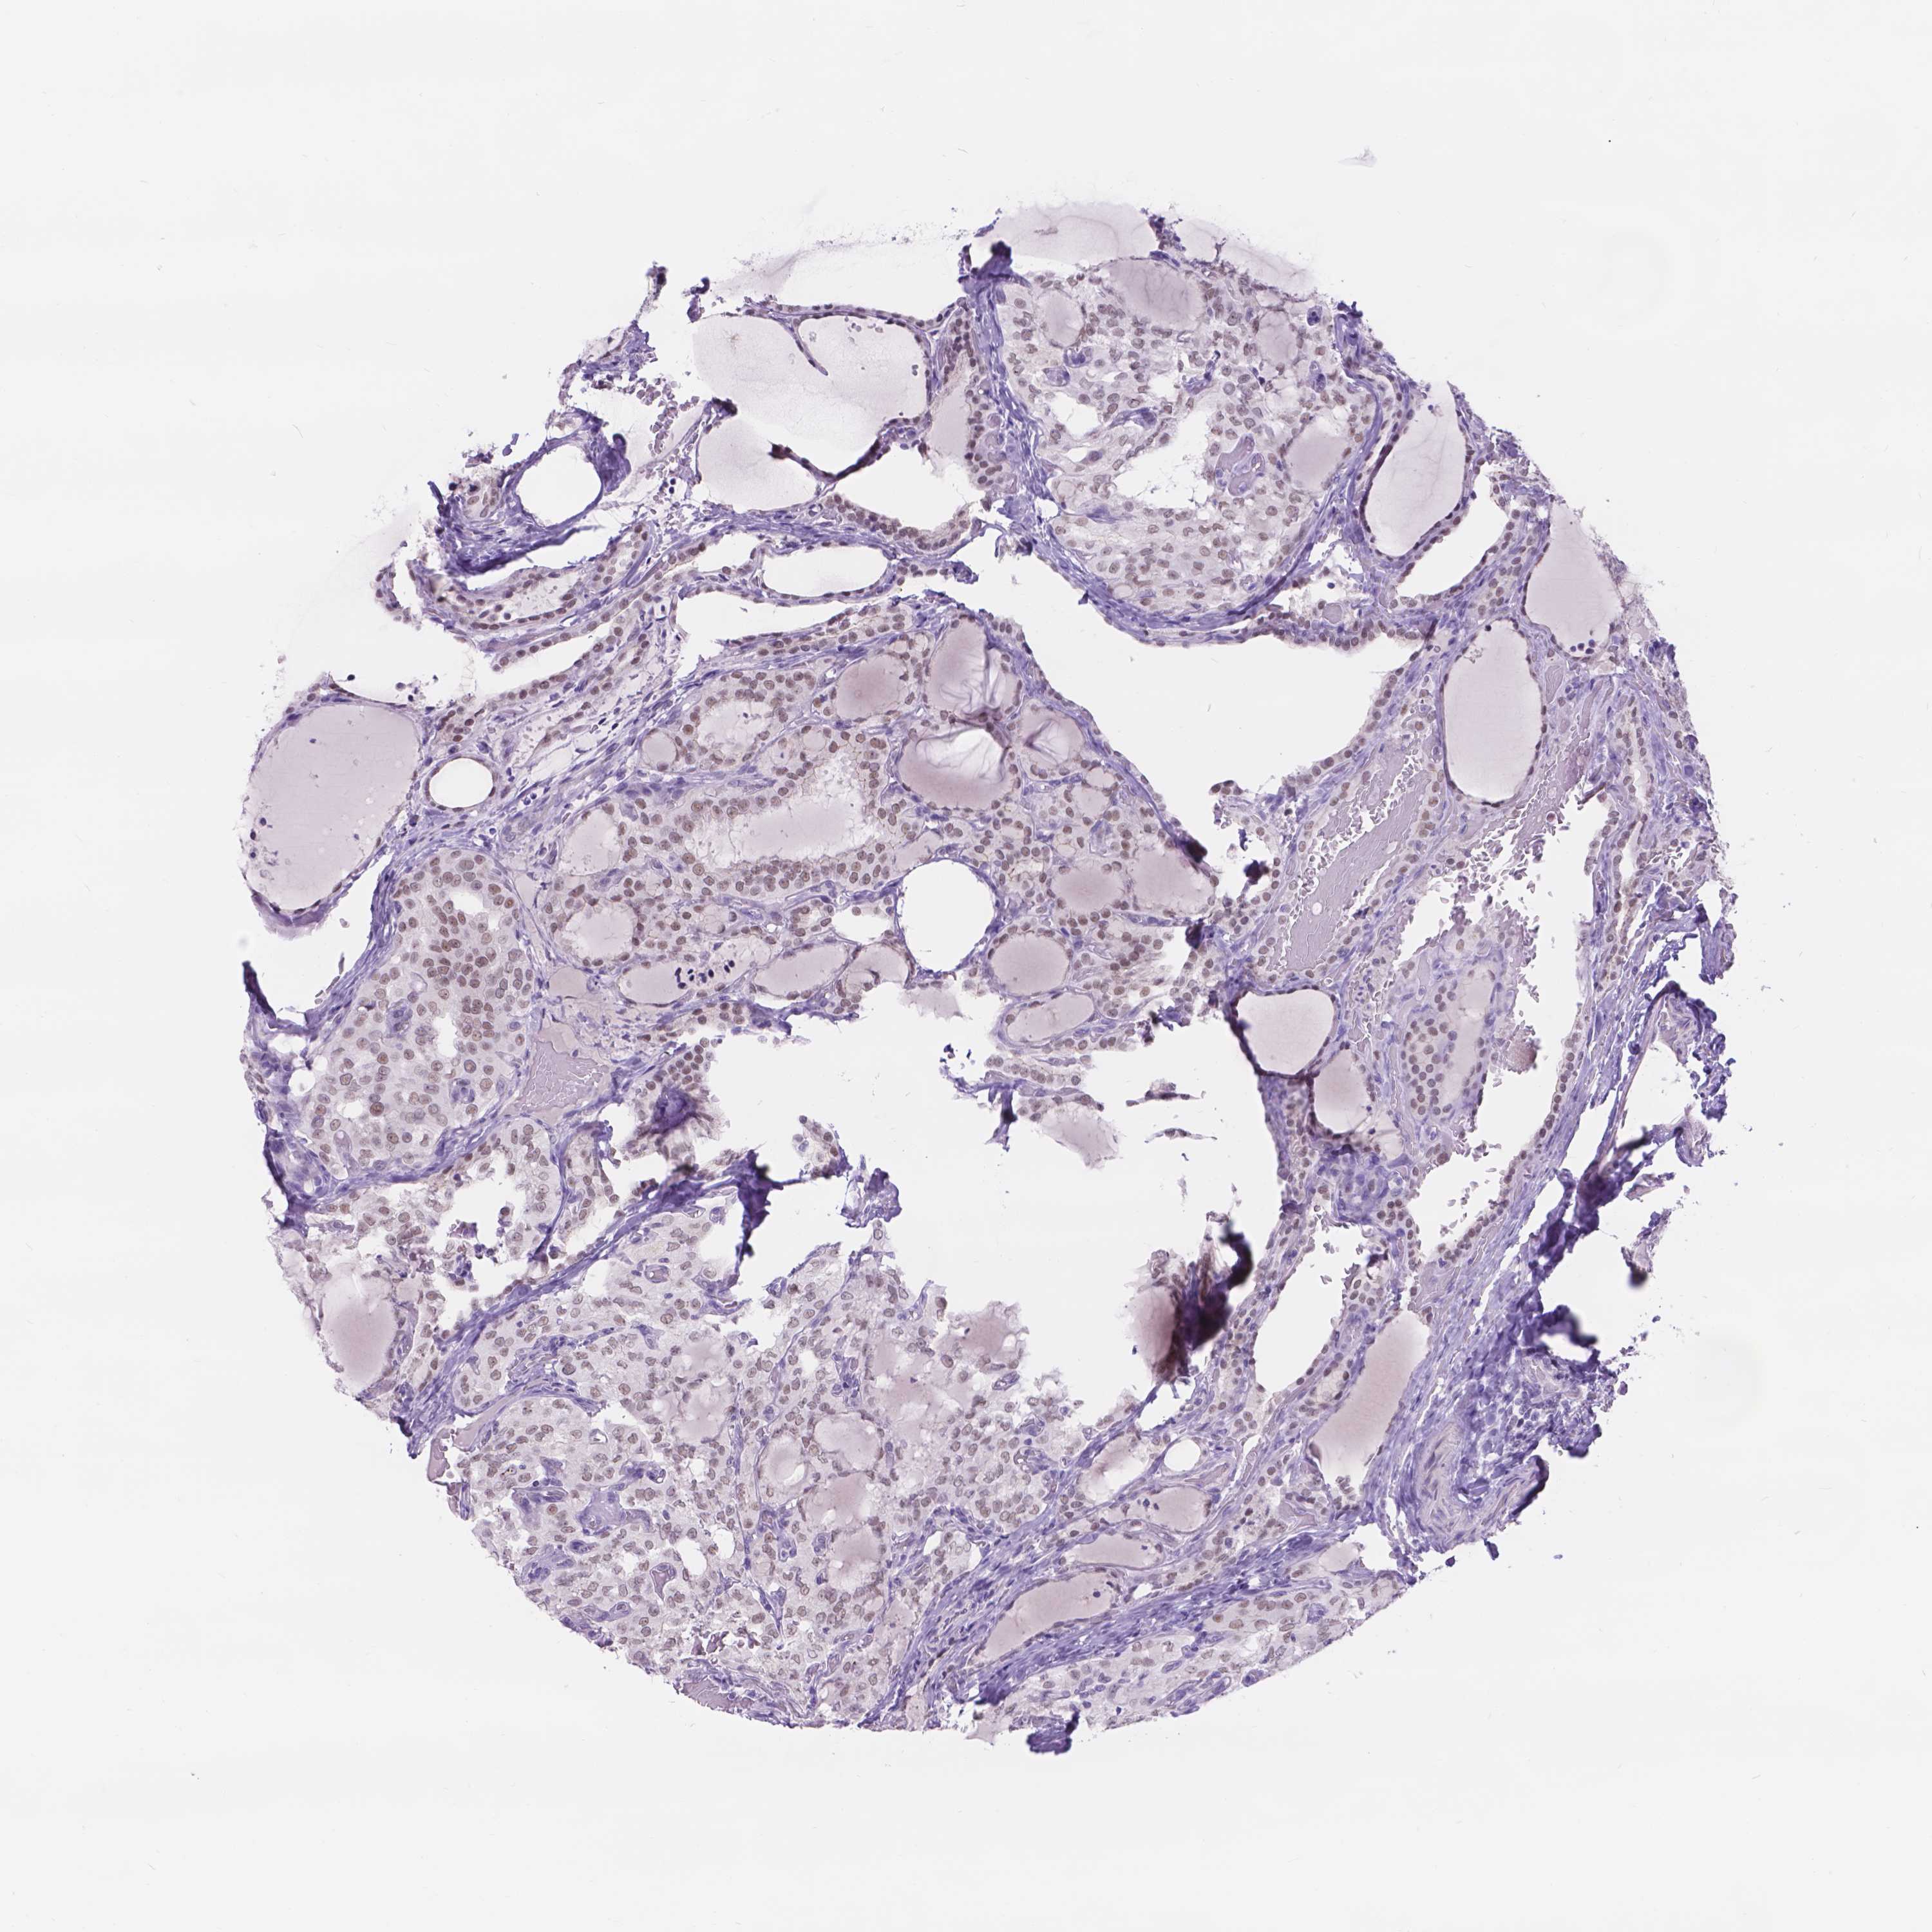

THYROID CANCER - Protein expressioni

A mouse-over function shows sample information and annotation data. Click on an image to view it in a full screen mode. Samples can be filtered based on level of antibody staining by selecting one or several of the following categories: high, medium, low and not detected. The assay and annotation is described here.

Note that samples used for immunohistochemistry by the Human Protein Atlas do not correspond to samples in the TCGA dataset.

Antibody stainingi

Antibody staining in the annotated cell types in the current human tissue is reported as not detected, low, medium, or high, based on conventional immunohistochemistry profiling in selected tissues. This score is based on the combination of the staining intensity and fraction of stained cells.

Each image is clickable and will lead to virtual microscopy that enables deeper exploration of all samples and also displays staining intensity scores, fraction scores and subcellular localization as well as patient and tissue information for each sample.

Antibody HPA069552

Staining

High

Medium

Low

Not detected

Intensity

Strong

Moderate

Weak

Negative

Quantity

>75%

75%-25%

<25%

None

Location

Nuclear

Cytoplasmic/membranous

Cytoplasmic/membranous,nuclear

Papillary adenocarcinoma, NOS

Papillary adenoma metastatic

Follicular adenoma carcinoma, NOS